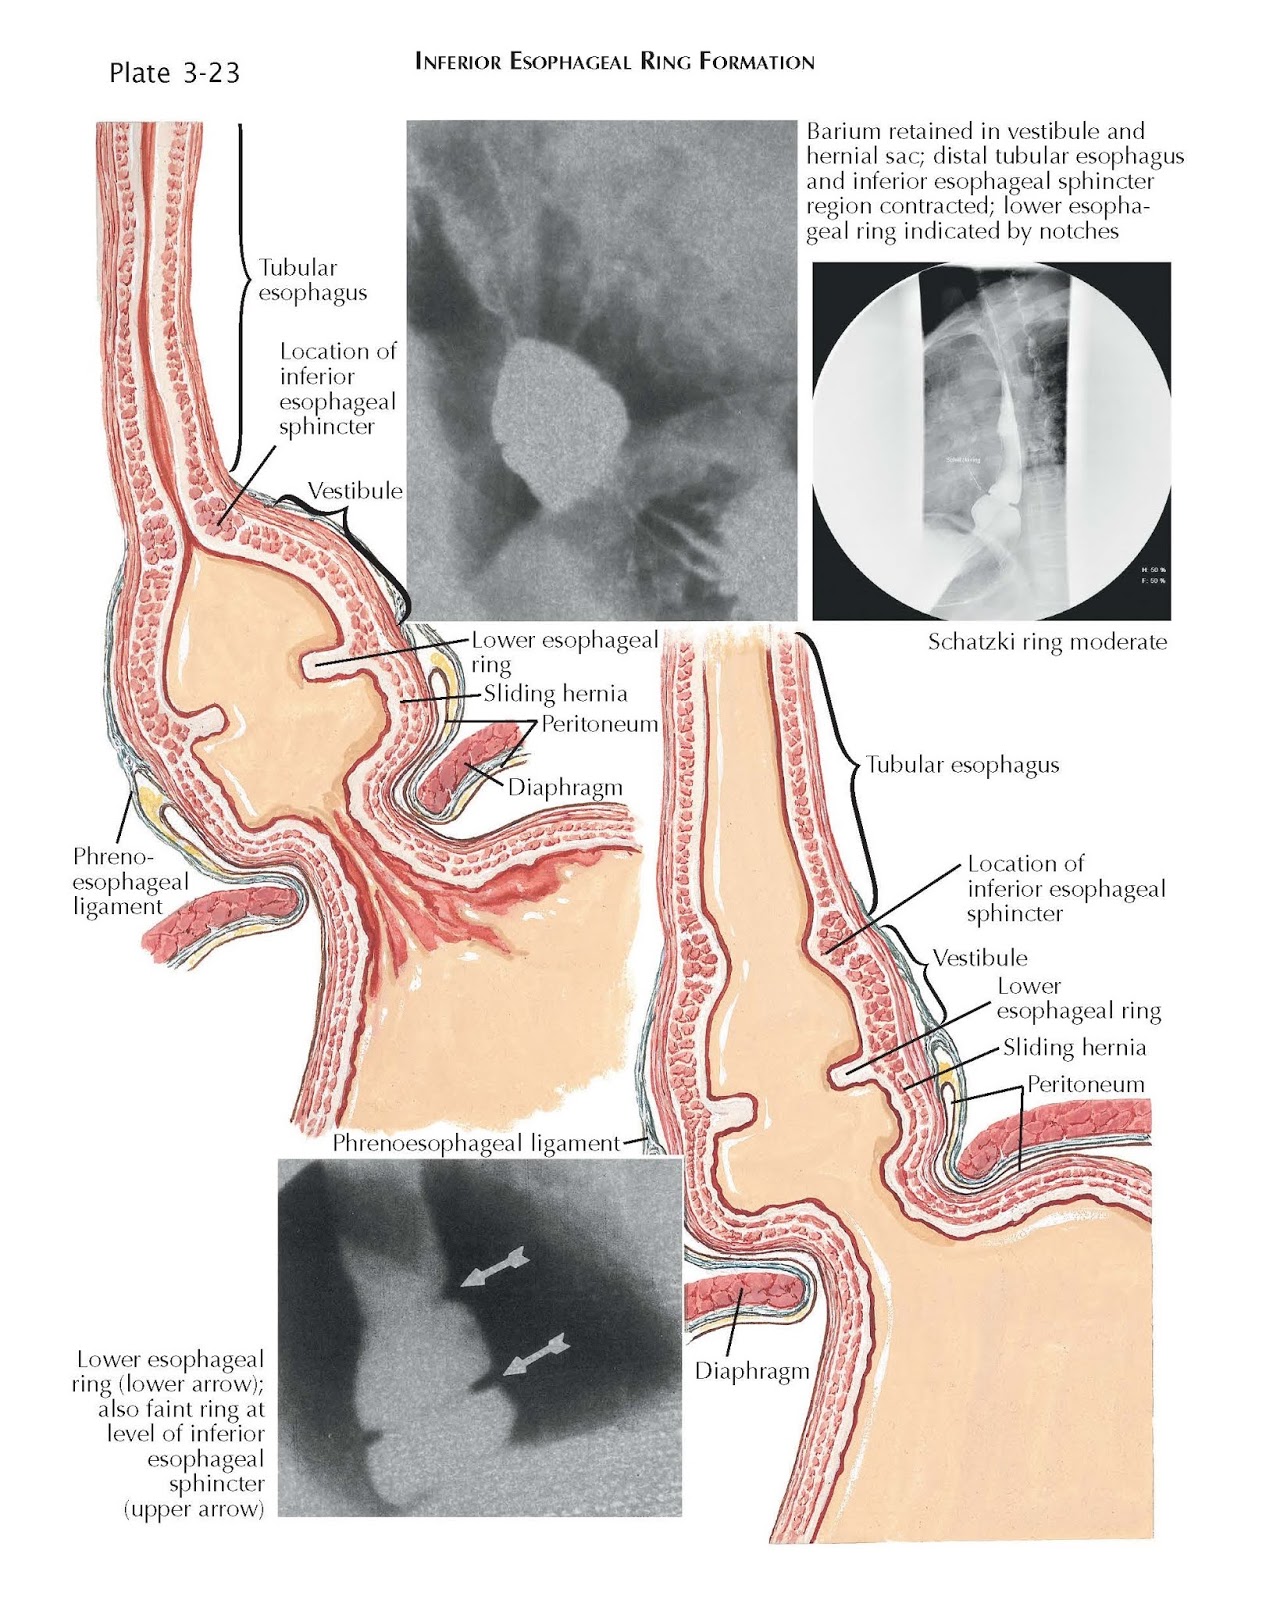

From www.pediagenosis.com

Inferior Esophageal Ring Formation pediagenosis Endoscopy Of The Esophagus And Duodenum It is a test that enables doctors to examine the upper. Esophagogastroduodenoscopy (egd) is a diagnostic endoscopic procedure that includes visualization of the oropharynx,. Esophagogastroduodenoscopy (egd) is a test to examine the lining of the esophagus, stomach, and first part of the small intestine. Upper gastrointestinal (gi) endoscopy (esophagogastroduodenoscopy [egd]) includes visualization of the oropharynx,. An upper endoscopy is also. Endoscopy Of The Esophagus And Duodenum.